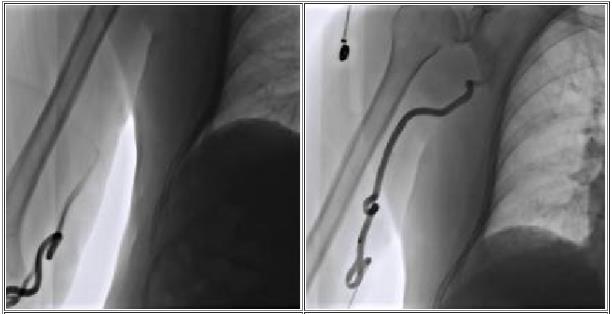

• In patients with long arms or upper body, standard catheters not even reach to the level of the renal arteries.

• should be equipped with long introducer sheaths (up to 110 cm) and long-shaft balloons and stents. Currently, the shaft length for balloons is limited to 150 cm and for the stents to 135 cm